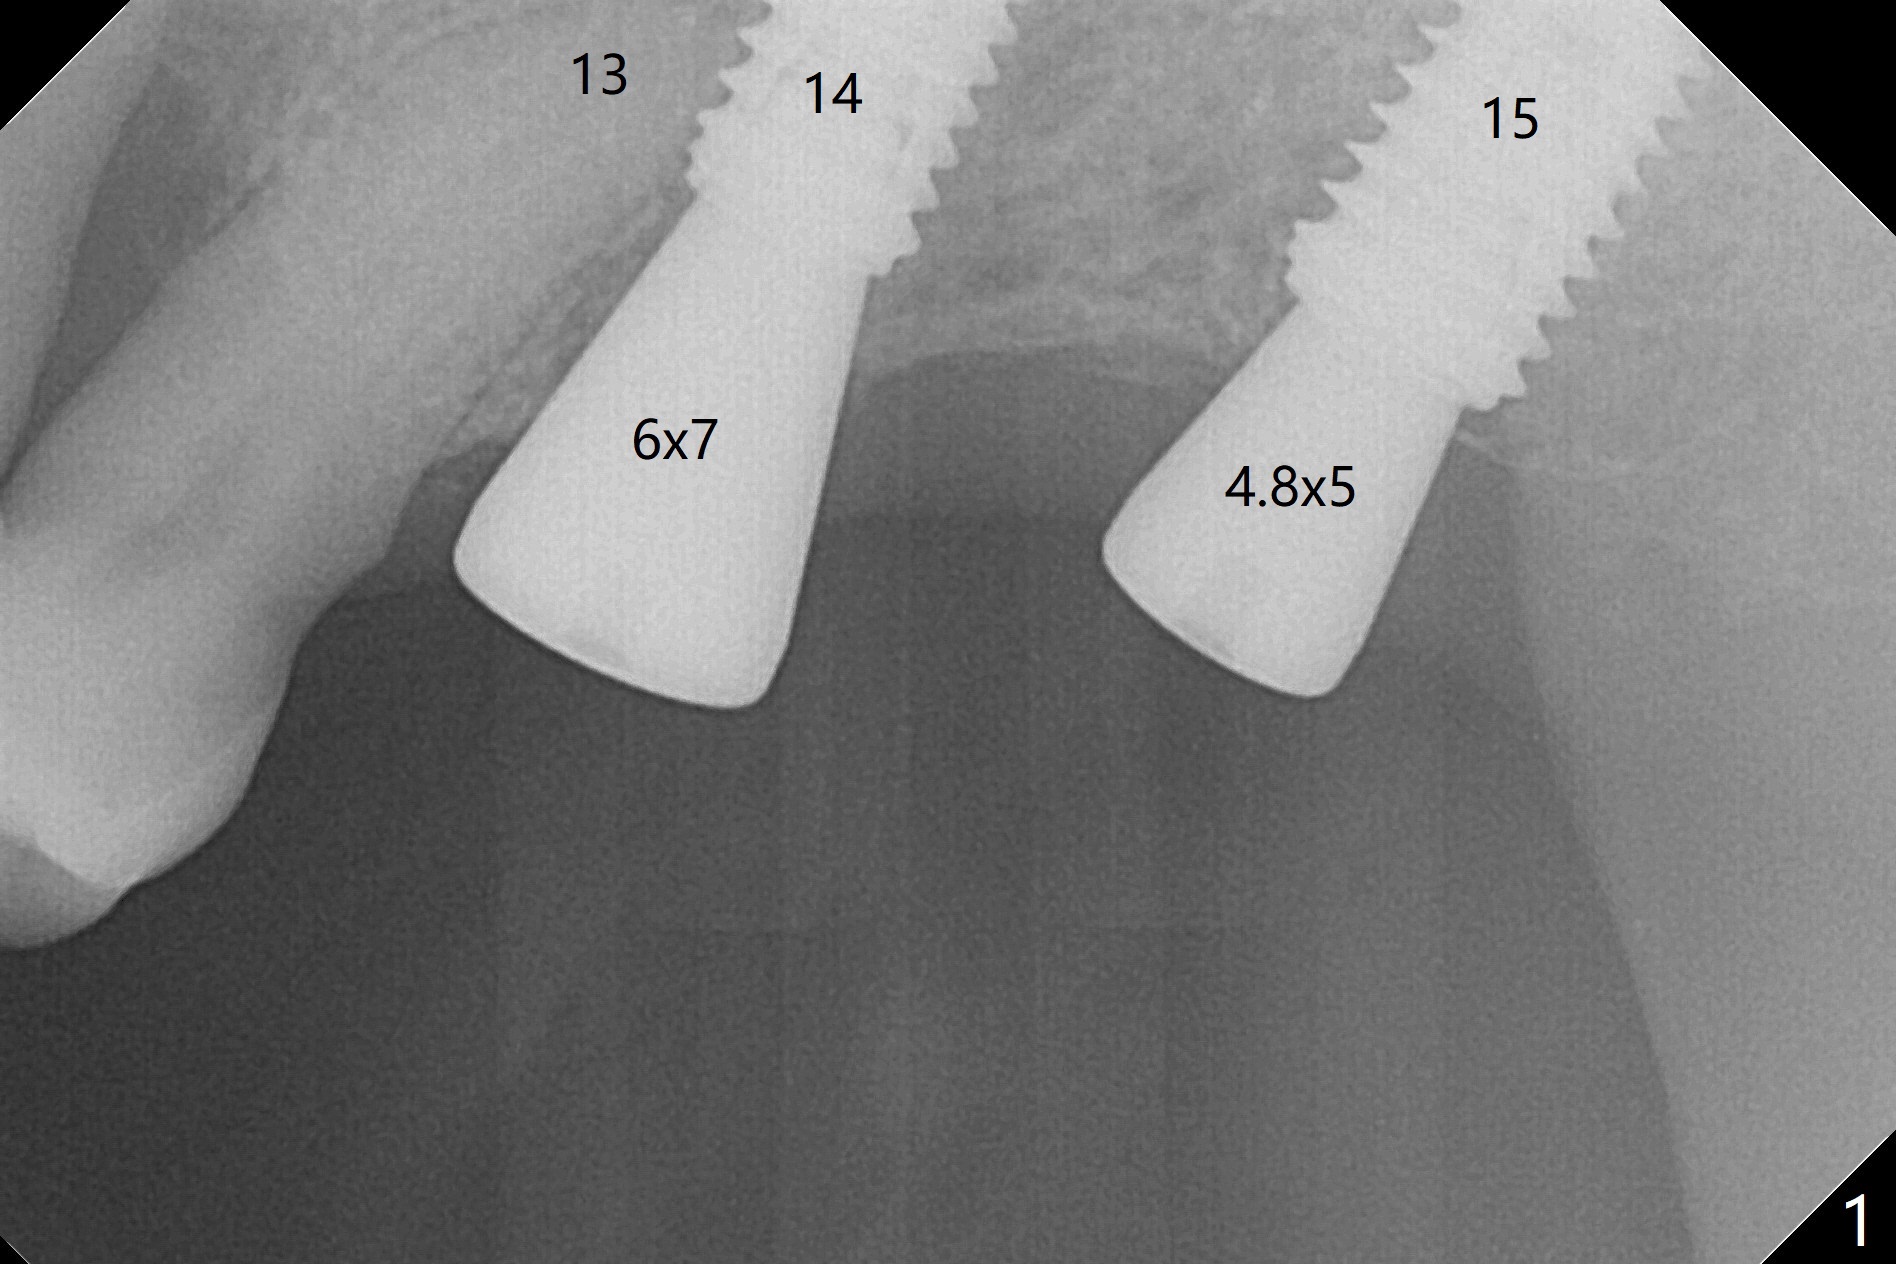

Immediately postop PA (Fig.1) and panoramic X-ray (Fig.2) show that the implant at #14 is close to the root of the tooth #13.  Clinic exam and CBCT (Fig.3,4) demonstrate a reasonable separation.  The trajectory of #14 osteotomy may be altered while using 2.8 mm round drill for 7-9 mm for sinus lift (free hand).  There is no bone loss 8 months postop (Fig.5).

#15 looks good as planned and #14 seems quite close to the neighboring tooth and quite off from the planed position.